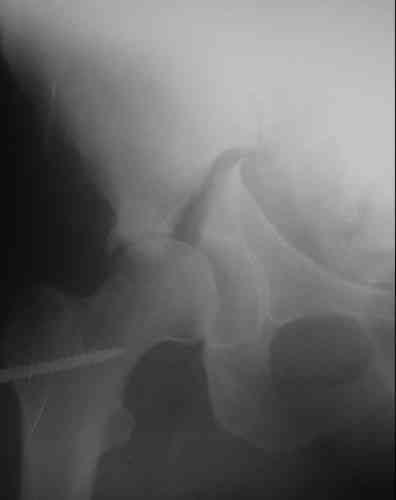

Пациентка 38 лет. В результате ДТП 02.09.06 получила поперечный перелом правой вертлужной впадины, центральный вывих правого бедра, разрыв правого крестцово-подвздошного сустава.

На показанных снимках повреждение правого КПС не очень заметно...

У меня создалось впечатление( одна из РГ), что участок суставной поверхности нагрузочной зоны вертлужной впадины вдавлен( постарайтесь сделать КТ). Если это подтвердиться, то из внутритазового доступа отрепонировать будет невозможно.

скорее задний тип

в этой ситуации не требует фиксации